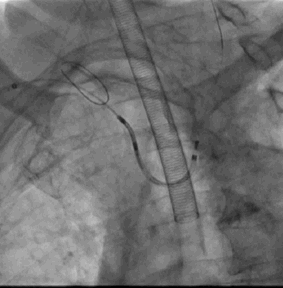

2. 经右桡动脉置入Sentinel CPS系统,释放于头臂干、左颈总动脉位

6. Sentinel CPS系统

Sentinel CPS系统在另一患者中應用捕抓到的左心耳血栓